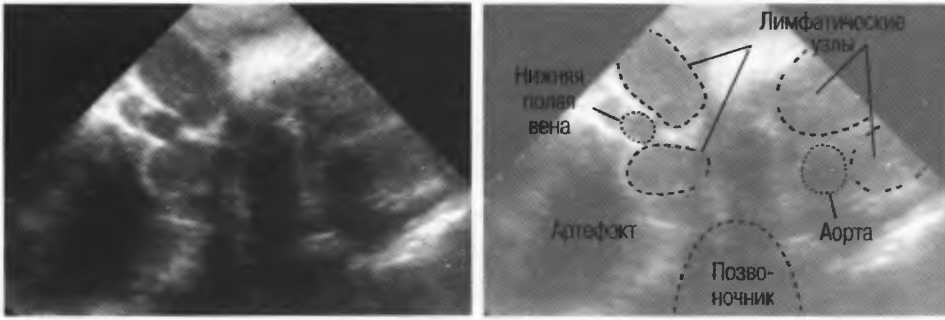

1. Подготовка

Пациент не должен пить и есть в течение 8 ч перед исследованием. Если жидкость необходима для предотвращения дегидратации, можно давать пациенту только воду. При острой симптоматике исследование можно проводить без подготовки. Детям, если позволяют клинические условия, пища и вода не даются в течение 3 ч до исследования.

При более углубленном исследовании, если нет клинических противопоказаний, может быть полезным дополнительный прием воды, особенно при исследовании поджелудочной железы, нижних отделов живота и таза.

2. Положение пациента. Пациент может лежать в удобной позе на спине. Под голову можно положить маленькую подушку, в случае выраженного напряжения передней брюшной стенки подушечку можно поместить также под колени пациента.

Намажьте живот гелем.

Пациенту разрешается дышать спокойно, однако при исследовании отдельных органов требуется задержка дыхания на вдохе.

3. Выбор датчика. Используйте датчик 3,5 МГц для взрослых и датчик 5 МГц для детей и худых взрослых. Предпочтительны конвексные или секторные датчики.

4. Установите правильный уровень общей чувствительности. Начинайте исследования, поместив датчик центрально в верхней части живота под мечевидным отростком и попросите пациента глубоко вдохнуть и задержать дыхание на вдохе.

Поверните датчик направо до того, как начнет визуализироваться печень. Отрегулируйте чувствительность, чтобы изображение имело нормальную однородную зхоструктуру. Должна быть хорошо различима высокоэхогенная линия диафрагмы сразу за задними отделами печени (рис. 27а).

Воротная и печеночные вены должны визуализироваться как трубчатые структуры с анзхогенным просветом. Стенки воротной вены высокозхогенны, но стенки печеночных вен практически не видны (рис. 276).

Рис.27а. Продольный срез. Неизмененная печень и диафрагма.